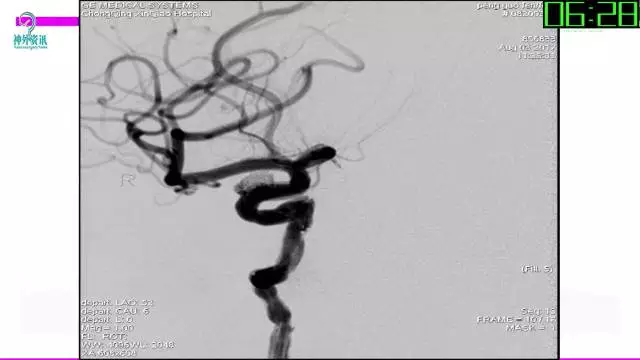

今天为大家分享的是“强生医疗CNV-神经介入专栏”第三十六期,由重庆第三军医大学附属新桥医院神经外科刘俊带来的“Galaxy弹簧圈在不规则动脉瘤中的临床应用”精彩讲课视频及PPT,欢迎观看。文章仅代表作者个人观点,如有不同见解,欢迎同道斧正!